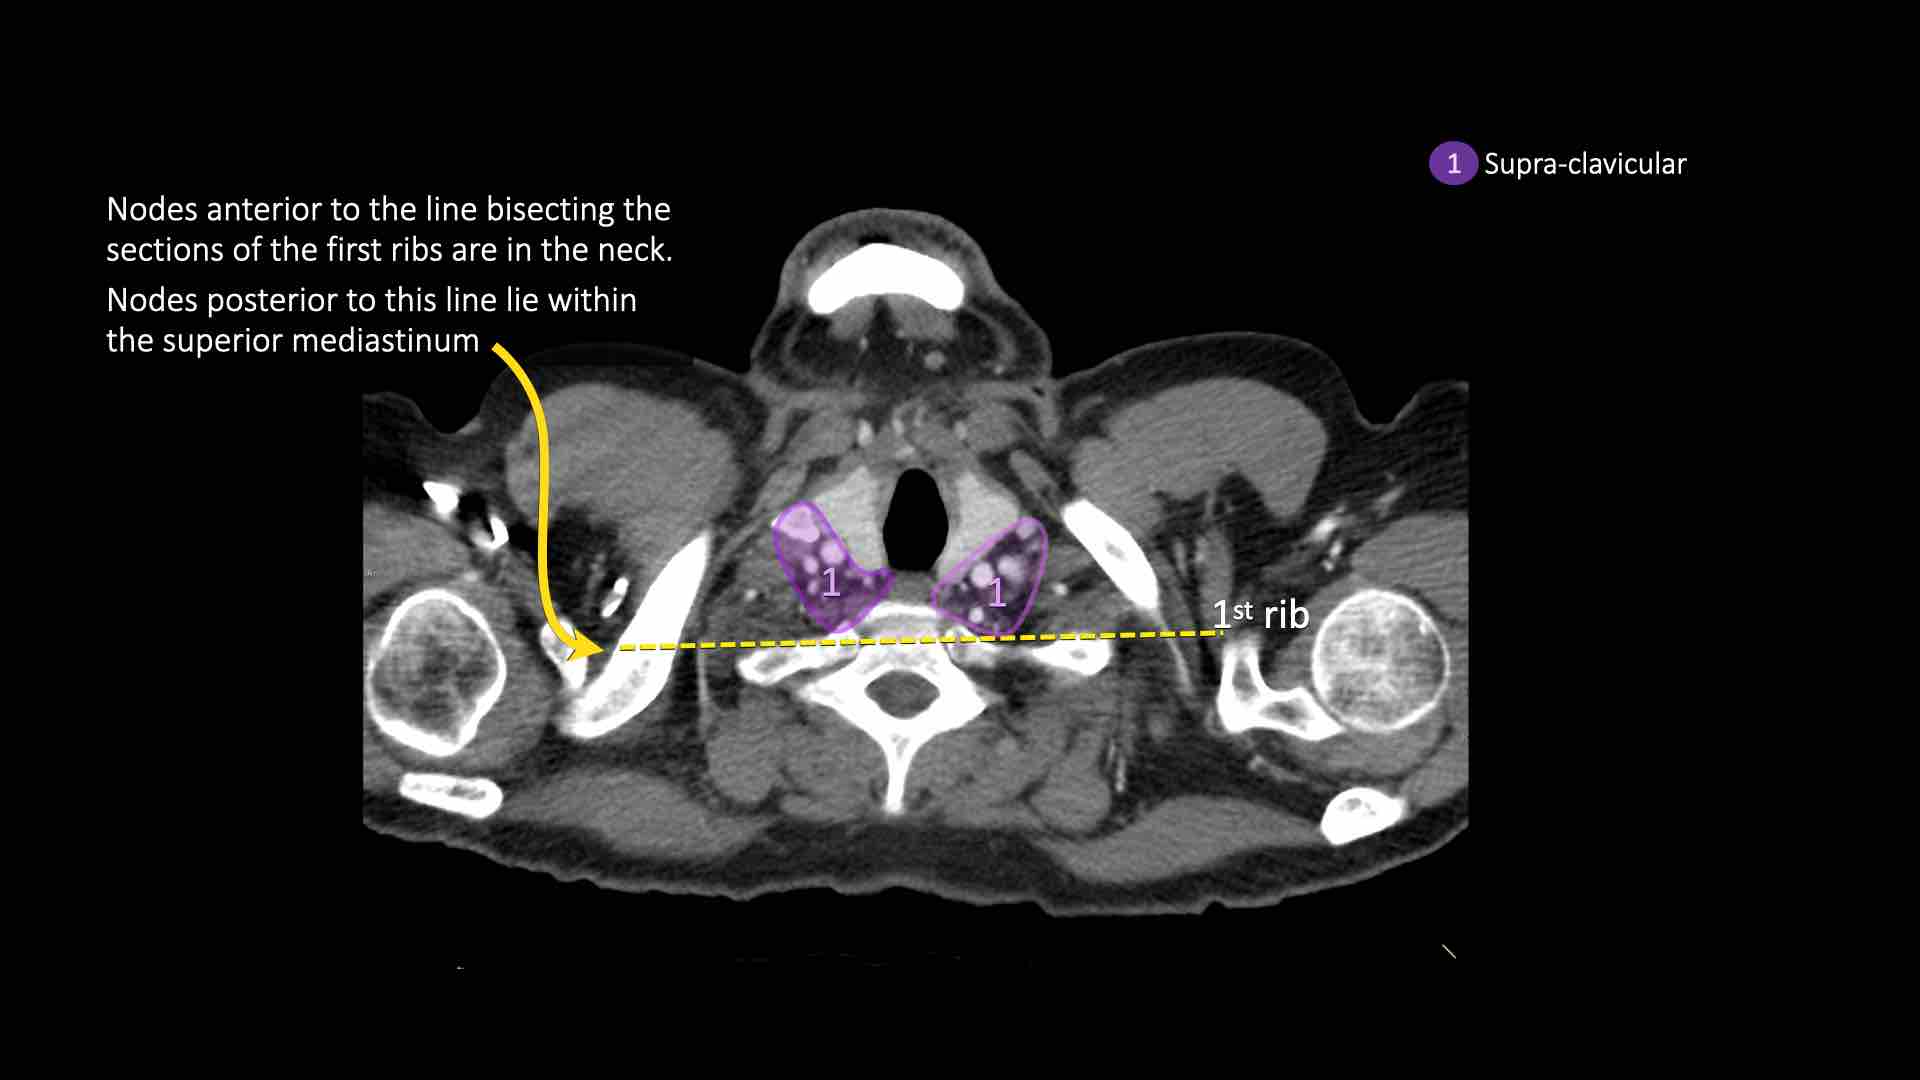

1. Hạch vùng thượng đòn

Bao gồm các hạch cổ thấp, thượng đòn và hạch khuyết ức.

Ranh giới trên: bờ dưới sụn nhẫn.

Ranh giới dưới: xương đòn và bờ trên cán ức.

Đường giữa khí quản là ranh giới phân chia giữa nhóm 1R và 1L.